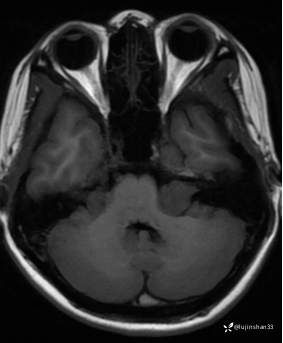

第一次术前颞骨CT及MRI: